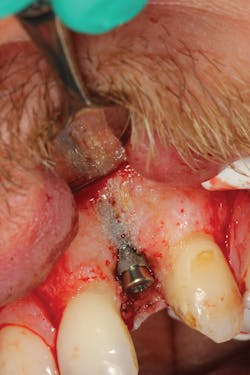

Because of this alveolar resorptive pattern after tooth extraction, bone grafting the extraction socket after tooth extraction procedures has become a solution that attempts to limit the amount of hard- and soft-tissue loss. There are many systematic reviews in the literature that compare the results of residual ridge dimension following tooth extraction after the use of a bone graft (with or without a membrane) versus extraction alone without grafting.7

• preserving tissue structure for subsequent dental implant therapy.Decision matrix

What bone grafting product?

Although there are many types of grafting products commercially available, choosing the right one may be difficult. An ideal bone graft substitute should be biomechanically stable; able to degrade within an appropriate time frame; exhibit osteoconductive, osteogenic, and osteoinductive properties; and provide a favorable environment for invading blood vessels and bone-forming cells.10